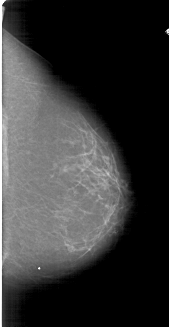

A_1800_1.RIGHT_CC

RIGHT_CC LINES 6196 PIXELS_PER_LINE 3196 BITS_PER_PIXEL 12 RESOLUTION 43.5 NON_OVERLAY